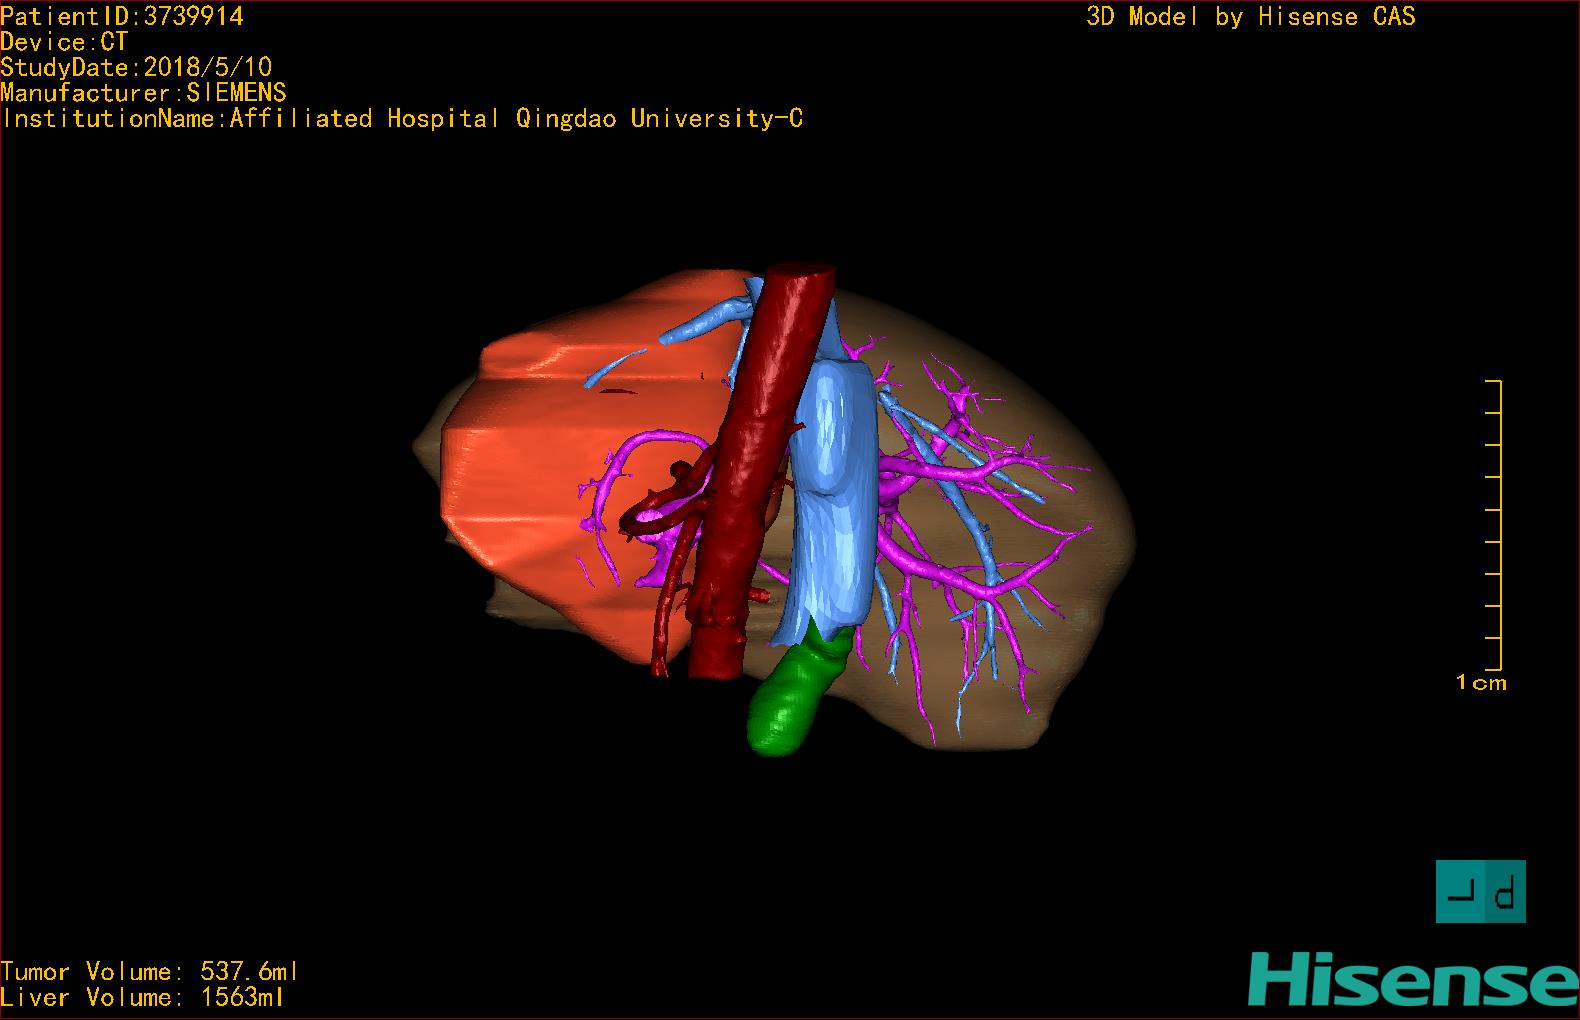

实验室检查: 血常规:WBC 4.89*109/L,RBC 3.64*1012/L, HB 119.00g/L, HCT 35.40%,PLT 123*109/L,RET% 0.48%, RET 0.017*1012/L, IRF 2.00%生化全套:ALT 56.00U/L AST 60.00U/L, LDH 312.00U/L TP 72.08g/L ALB 32.44g/L, GGT 101.00U/L,TBA 21.90umol/L,A/G 0.82,ADA 23.00U/L, PAB 94.20mg/L, CHE 5405.00U/L 肿瘤标志物:CEA 2.80ng/mL CA19-9 11.46U/ml 肝炎全套: HAV-IgM 0.21S/CO, HBcIgM 0.330S/CO, HCV-cAg 0.08S/CO, HEV-IgM 0.03S/CO, HBeAg 6.000S/CO 诊疗过程: CT结果输入海信CAS系统后行3D重建及手术规划后,于2018-5-17局麻下行“经皮肝动脉造影术+肝动脉化疗栓塞术”手术治疗 术前三维重建及手术方案设计: 将0.625mm双源薄层CT资料的静脉期和动脉期Dicom格式文件导入海信CAS系统。 通过调节窗宽窗位调整CT序号,对肿瘤,肝实质,胆囊,下腔静脉,肿瘤,肝动脉、门静脉及肝静脉等进行三维重建;系统自动计算肿瘤体积和肝脏体积。肝脏体积为1563ml,肿瘤体积为537.6ml,通过比对50-60岁正常肝脏体积为1343.28±246.69ml。 手术步骤: 常规准备后,患者仰卧于DSA手术床。常规双侧股动脉区域消毒,铺巾。2%利多卡因局部麻醉右侧股动脉区成功后,应用Seldinger技术穿刺右侧股动脉,置入5F动脉鞘。送5F 肝导管至腹腔干、肝动脉造影,肝区可见团块状及多发结节状肿瘤染色、侵犯门静脉左支。静脉推注维瑞特5mg后,透视下将微导管分别超选择至各支肿瘤供血动脉内,应用雷替曲塞4mg+奥沙利铂50mg+表柔比星20mg +LP 10ml的混合液及适量350-560um明胶海绵进行栓塞,后造影示栓塞适量,退出导管、血管鞘,局部压迫10min,加压包扎。患者术中未诉不适,术后平车安返病房。随访情况: 患者术后3月复查上腹CT示肝左叶病变活性残留,腹腔内、腹膜后多发略大淋巴结,部分较前略减小,今患者为求进一步诊治,与我院再次行“肝动脉造影+经导管肝动脉栓塞术”,术后2周无明显不适 术前CT检查:动脉期

术前三维重建:重建图片.jpg)